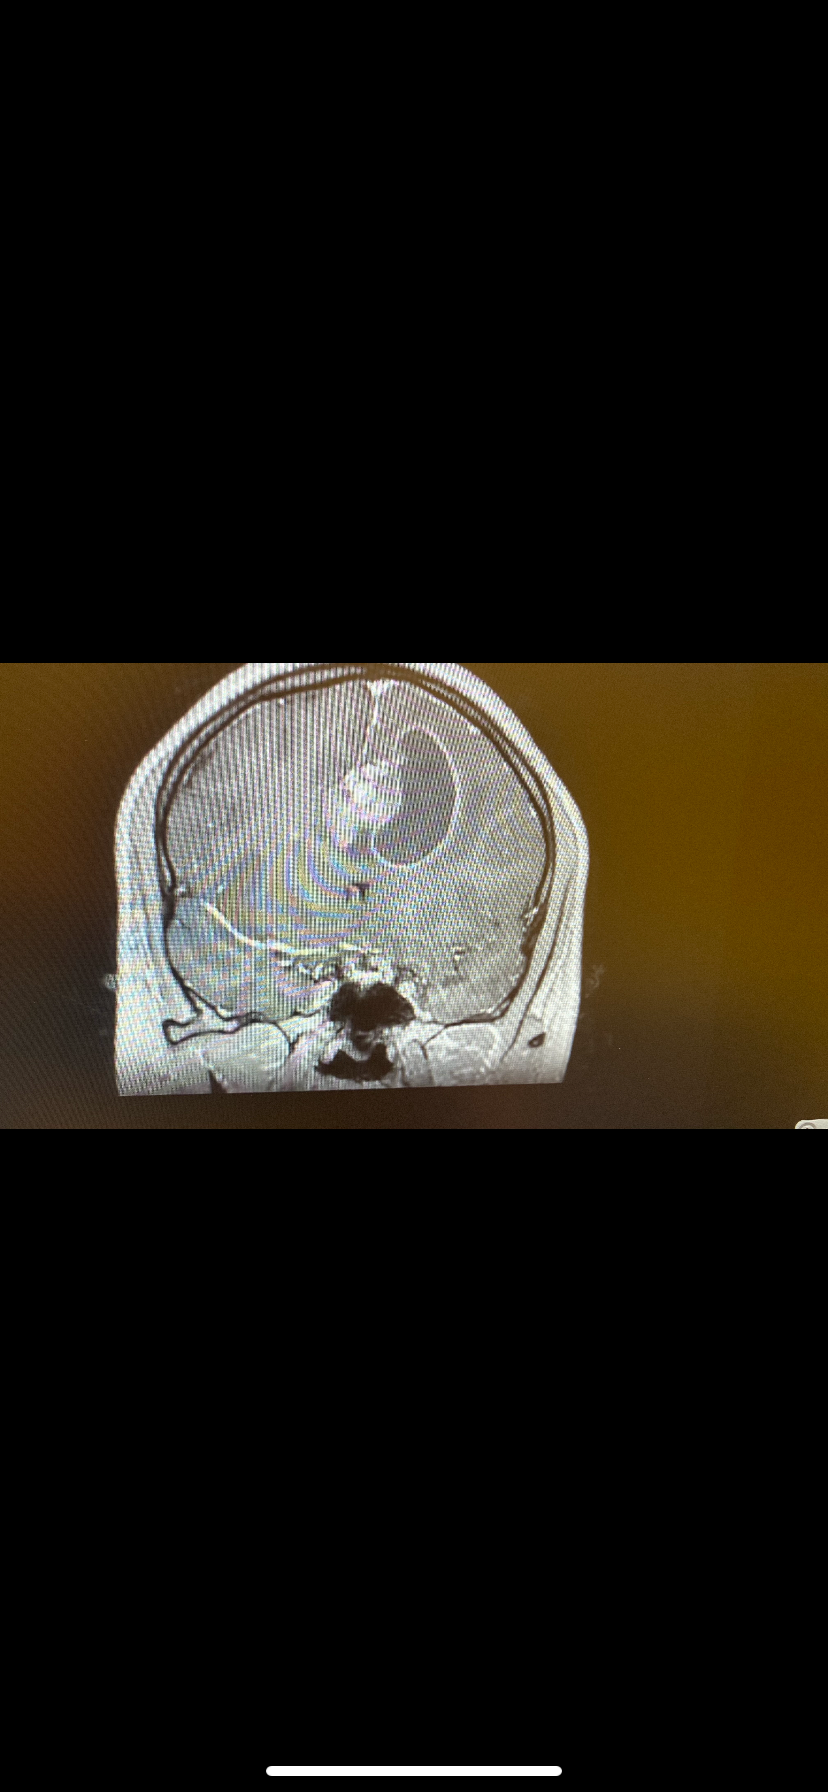

This isn’t the kind of thing you think you’ll ever find yourself having to do. My sweet cousin Rachel Nix is 26 years old. We just found out that she will be having brain surgery next Wednesday because they found a 2-inch tumor on her frontal lobe that has caused massive inflammation and fluid on her brain. They will test it after removal to see if it is benign. It has negatively affected her in many different ways, causing weakness on her whole right side, migraines, and confusion. She isn’t able to work or even drive. She is on anti-seizure medication as well. I was hoping to be able to gift her, from the generosity and kindness of others, some financial help. This is a hard hit for her and I wish I could ease some of her stress. Fingers crossed this finds the right kind of people. And if anything, prayers are also appreciated. Thank you, everyone, for visiting this profile ❤️